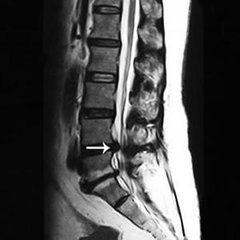

腰椎间盘脱出是什么?腰椎间盘脱出属于腰椎间盘突出症中的一个疾病发展阶段,并且脱出属于腰椎间盘突出症中较严重阶段,椎间盘内的髓核突破纤维环,进入椎管,对神经造成严重压迫,但尚未有效从纤维环中脱离。没有髓核做支撑,相邻脊椎骨长时间摩擦还会导致骨质增生病症即骨刺。因此腰椎间盘脱出病症非常严重,如果不及时治好,还会导致关节性疾病如骨刺等产生,患者对该病一定不能掉以轻心,应积极寻求治疗方案进行治疗。》》》百看不如一问,咨询专家如何对症治疗

(1)椎管型:或称后型,指髓核穿过纤维环向椎管方向突出者。脱出的髓核停于后纵韧带前方者,称为“椎间盘突出”;穿过后纵韧带抵达椎管内者,则称“椎间盘脱出”。》》》百看不如一问,咨询专家如何对症治疗

(2)椎体型:即指变性的髓核穿过下方(多见)或上方(少见)纤维环,再穿过软骨板呈垂直状或斜向进入椎体中部或椎体边缘的髓核突出。 》》》百看不如一问,咨询专家如何对症治疗